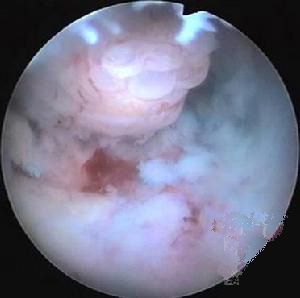

2、宮腔鏡,融診斷與治療於一體,一些較難處理的婦科疾病能直觀、簡單、安全地解決。對於膜性積膿、纖維肌性積膿可在宮腔鏡下分離或用手術剪除;而對於結締組織樣緻密粘連則需在B超或腹腔鏡監護下行電切分離術,術後放置宮內節育器或蛋白膠防止再積膿,使病人恢復月經來潮,達到生育目的。

1、子宮腔鏡檢查可了解有無宮腔積膿,並確定粘連部位、範圍、程度及粘連的組織。各組粘連的特點為:子宮內宮腔積膿與周圍的內膜很相似;肌纖維粘連最常見,其特點為有一薄層子宮內膜覆在上面,表面有很多腺體開口;而結締組織粘連則表面無內膜形成。